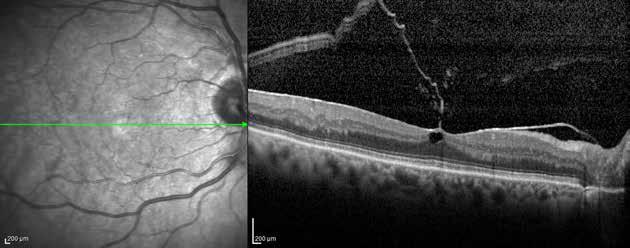

Figure 2. Multimodal imaging of right eye of a male diabetic patient affected by PDR and DME. 2A-B) UWF pseudocolor retinography (Optos Silverstone, Optos, UK) and corresponding magnification of macular region showing diffuse hard exudates and intraretinal hemorrages; 2C) OCT (Heidelberg Spectralis, Heidelberg Engineering Inc., Germany) displaying diffuse center-involving DME; 2D-E) Late phase UWF FA (Optos Silverstone, Optos, UK) and corresponding magnification of macular region presenting extense breakdown of BRB with perivascular leakage and non-perfusion areas, pooling effect compatible with MA and masking effect due to pre-retinal hemorrhages. Two leakage spots associated to possible NVs close to inferior vascular arcade; 2F) 3x3 B-scan OCT-A (Zeiss PLEX Elite 9000, Carl Zeiss, Germany) showing flow signal within pre-retinal NV.

Figure 3. Multimodal imaging of a male diabetic patient affected by PDR and DME that has already been treated by incomplete laser photocoagulation therapy. 3A) UWF pseudocolor retinography displaying hard exudates and intraretinal hemorrhages within vascular arcades and peripheral laser photocoagulation therapy; 3B) UWF SS-OCT showing focal center-involving DME; 3C) Late phase UWF FA (describing mild BRB disruption with 2 leakage areas compatible with NV along inferior vascular arcade; 3D) 15x15 En-face WF-SS-OCTA presenting FAZ enlargement, diffuse capillary drop-out and temporal mid-peripheral retinal nonperfusion areas, and two pathological vascular networks associated to NVs.

Figure 4. Multimodal imaging of a female diabetic patient affected by PDR that has already undergone complete laser photocoagulation treatment. 4A) UWF pseudocolor retinography showing complete laser photocoagulation treatment until vascular arcades; 4B-C) 12x12 and 4E-F) en-face WF-SS-OCTA of diabetic patient (4B, 4E) presenting FAZ enlargement, diffuse capillary drop-out and inferior mid-peripheral retinal nonperfusion areas, as compared to healthy patient (4C, 4F; 4D) Late phase UWF FA displaying diffuse BRB breakdwon, with perivascular leakage and non-perfusion areas.

5. Multimodal imaging of a

diabetic patient affected by

5A) UWF pseudocolor retinography showing some hard exudates within and outside vascular arcades; 5B) Late phase UWF FA presenting far peripheral BRB rupture, with associated perivascular leakage and retinal ischemia, and diffuse pooling effect within telengectasic vessels; 5C) UWF SS-OCT, displaying some hard exudates close to optic disc.

OCT-A) (Figures 2-5).